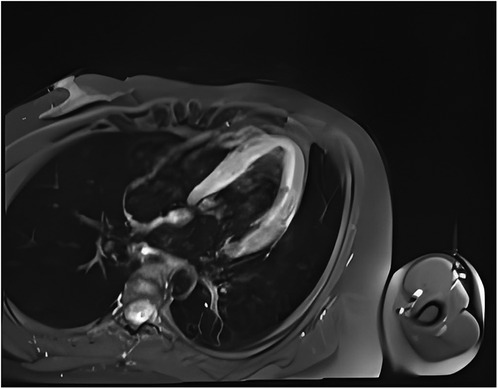

One day after admission, the patient's vital signs were unstable and her blood pressure remained low despite high doses of norepinephrine and m-hydroxyamine. Physical examination revealed scattered red maculae and maculopapules on the trunk and limbs, accompanied by iridoid lesions, blisters, and oral mucosal erosion (Figure 2). Echocardiography examination indicated a significant decrease in Ejection fraction (24%). A review of laboratory tests showed: WBC 6.6 × 109/L, CRP 20.2 mg/L, ALT 225 U/L, LDH 658 U/L, cTnI 20.9 ng/ml, CK 803 U/L, Lactate 6.62 mmol/L, NT-proBNP 6,690 ng/L. Considering the risk of cardiac arrest remains high, endotracheal intubation, V-A ECMO, and emergency coronary angiography were performed. Coronary angiography showed no obvious coronary vessel stenosis (Figure 3). At the same time, we performed extensive hematological tests to determine the cause of the erythema multiforme. Blood cultures were negative for bacteria and fungi. Immunological tests such as antinuclear antibodies, anti-double-stranded DNA antibodies and rheumatoid factors were negative. COVID-19 polymerase chain reaction was negative. HIV, Hep A, B, C and Treponema pallidum serologies were negative. Coxsackie virus, adenovirus, influenza A virus, influenza B virus, human parainfluenza virus, respiratory syncytial virus, Mycoplasma pneumoniae, chlamydia pneumoniae were negative. However, Chemiluminescence showed that herpes simplex virus-1 (HSV-1) was positive. Therefore, we considered that the patient had severe myocarditis and erythema multiforme due to infection with HSV-1 virus. We gave acyclovir needle antiviral and methylprednisolone needle anti-inflammatory. After the initiation of ECMO, the patient's blood pressure significantly increased and gradually stabilized at a systolic blood pressure of 90–168 mmHg and a diastolic blood pressure of 64–112 mmHg. Arterial blood gas analysis showed a significant improvement in acidosis. Therefore, we discontinued all vasoactive medications on the second day following the initiation of ECMO. Four days after the initiation of ECMO, the flow rate was reduced to 1.2 L/min, the patient's blood pressure remained relatively stable, blood gas analysis indicated good tissue perfusion, and follow-up echocardiography showed that the ejection fraction (EF) had recovered to 42%. We concluded that the criteria for ECMO withdrawal had been met, and ECMO was removed four days after its initiation. The day after ECMO was removed, the patient was then scheduled for a cardiac magnetic resonance imagery (CMRI) examination. Cardiac magnetic resonance T2-weighted imaging shows diffuse hypersignal in the left ventricular wall (Figure 4). Finally, the patient's symptoms gradually improved, the rash gradually disappeared on the seventh day, and she was discharged successfully after 2 weeks of treatment. The specific clinical process is shown in Supplementary Image 1. The patient has now been under observation for a period of one year, during which time she has attended five outpatient reviews at the hospital. No significant abnormalities have been observed in the patient's skin, troponin levels, electrocardiogram, or cardiac ultrasound. Furthermore, the patient has not continued any medications for the treatment of ring erythematosis or myocarditis.

Figure 4. Cardiac magnetic resonance T2-weighted imaging shows diffuse hypersignal in the left ventricular wall.

Myocarditis, one of the most important diseases of cardiovascular disease, used to have an incidence of 1 to 10 cases per 100,000 people per year (9). The highest risk was found in people aged 20 to 40 (10). Myocarditis can be caused by a variety of infectious and non-infectious causes. In infectious myocarditis, viruses are the most common cause. Viral myocarditis can be caused by adenovirus, enterovirus, COVID-19 and other viruses, but HSV-1 virus caused myocarditis is extremely rare. Bowles et al. used polymerase chain reaction (PCR) to analyze viral genomes in heart tissue and blood to identify common viral causes of myocarditis in different age groups. The viral genome was amplified in 239 (38%) of 624 patients with myocarditis, of which HSV infection accounted for only 0.8% of myocarditis (5). Previous basic studies have shown that myocarditis caused by HSV-1 infection is regulated by members of the TRIM protein family. TRIM29 could regulate the innate immunity to promote DNA virus HSV-1 infection (11) and loss of TRIM29 mitigates viral myocarditis by attenuating PERK-driven ER stress immune response (12). Additionally, TRIM18 deficiency is reported to control DNA virus HSV-1 infection and viral myocarditis (13). In this case, although acute myocardial infarction caused by coronary artery occlusion was excluded by coronary angiography, and myocarditis was diagnosed by troponin, magnetic resonance, and echocardiography, it was still difficult to diagnose the cause of myocarditis. The occurrence of multitype erythema provides the basis for the diagnosis of viral myocarditis and the direction for the targeted virus screening.